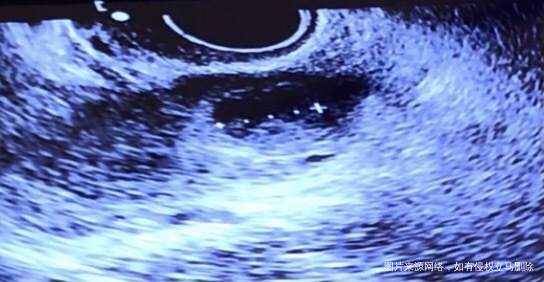

第一张图排卵前卵泡20毫米,第二张图排卵后第六天b超,卵泡外观扁了可是还有15毫米存在,本月就这一个大卵泡,请问这是排卵了吗?排完后这15毫米的东西为什么还存在?这是黄体吗?

你好,可能为黄体的,可以查孕酮,看是否排卵了。

正常情况下,排卵后就形成黄体。这个黄体的可能性大。2周后查hcg.

很有可能已经排卵了,后面这张图片很大的可能是黄体,既然做了卵泡监测指导同房,那就等14天以后抽血化验HCG来确定是否怀孕。

很有可能已经排卵了而形成的黄体,建议14天后检查hcg明确是否怀孕。